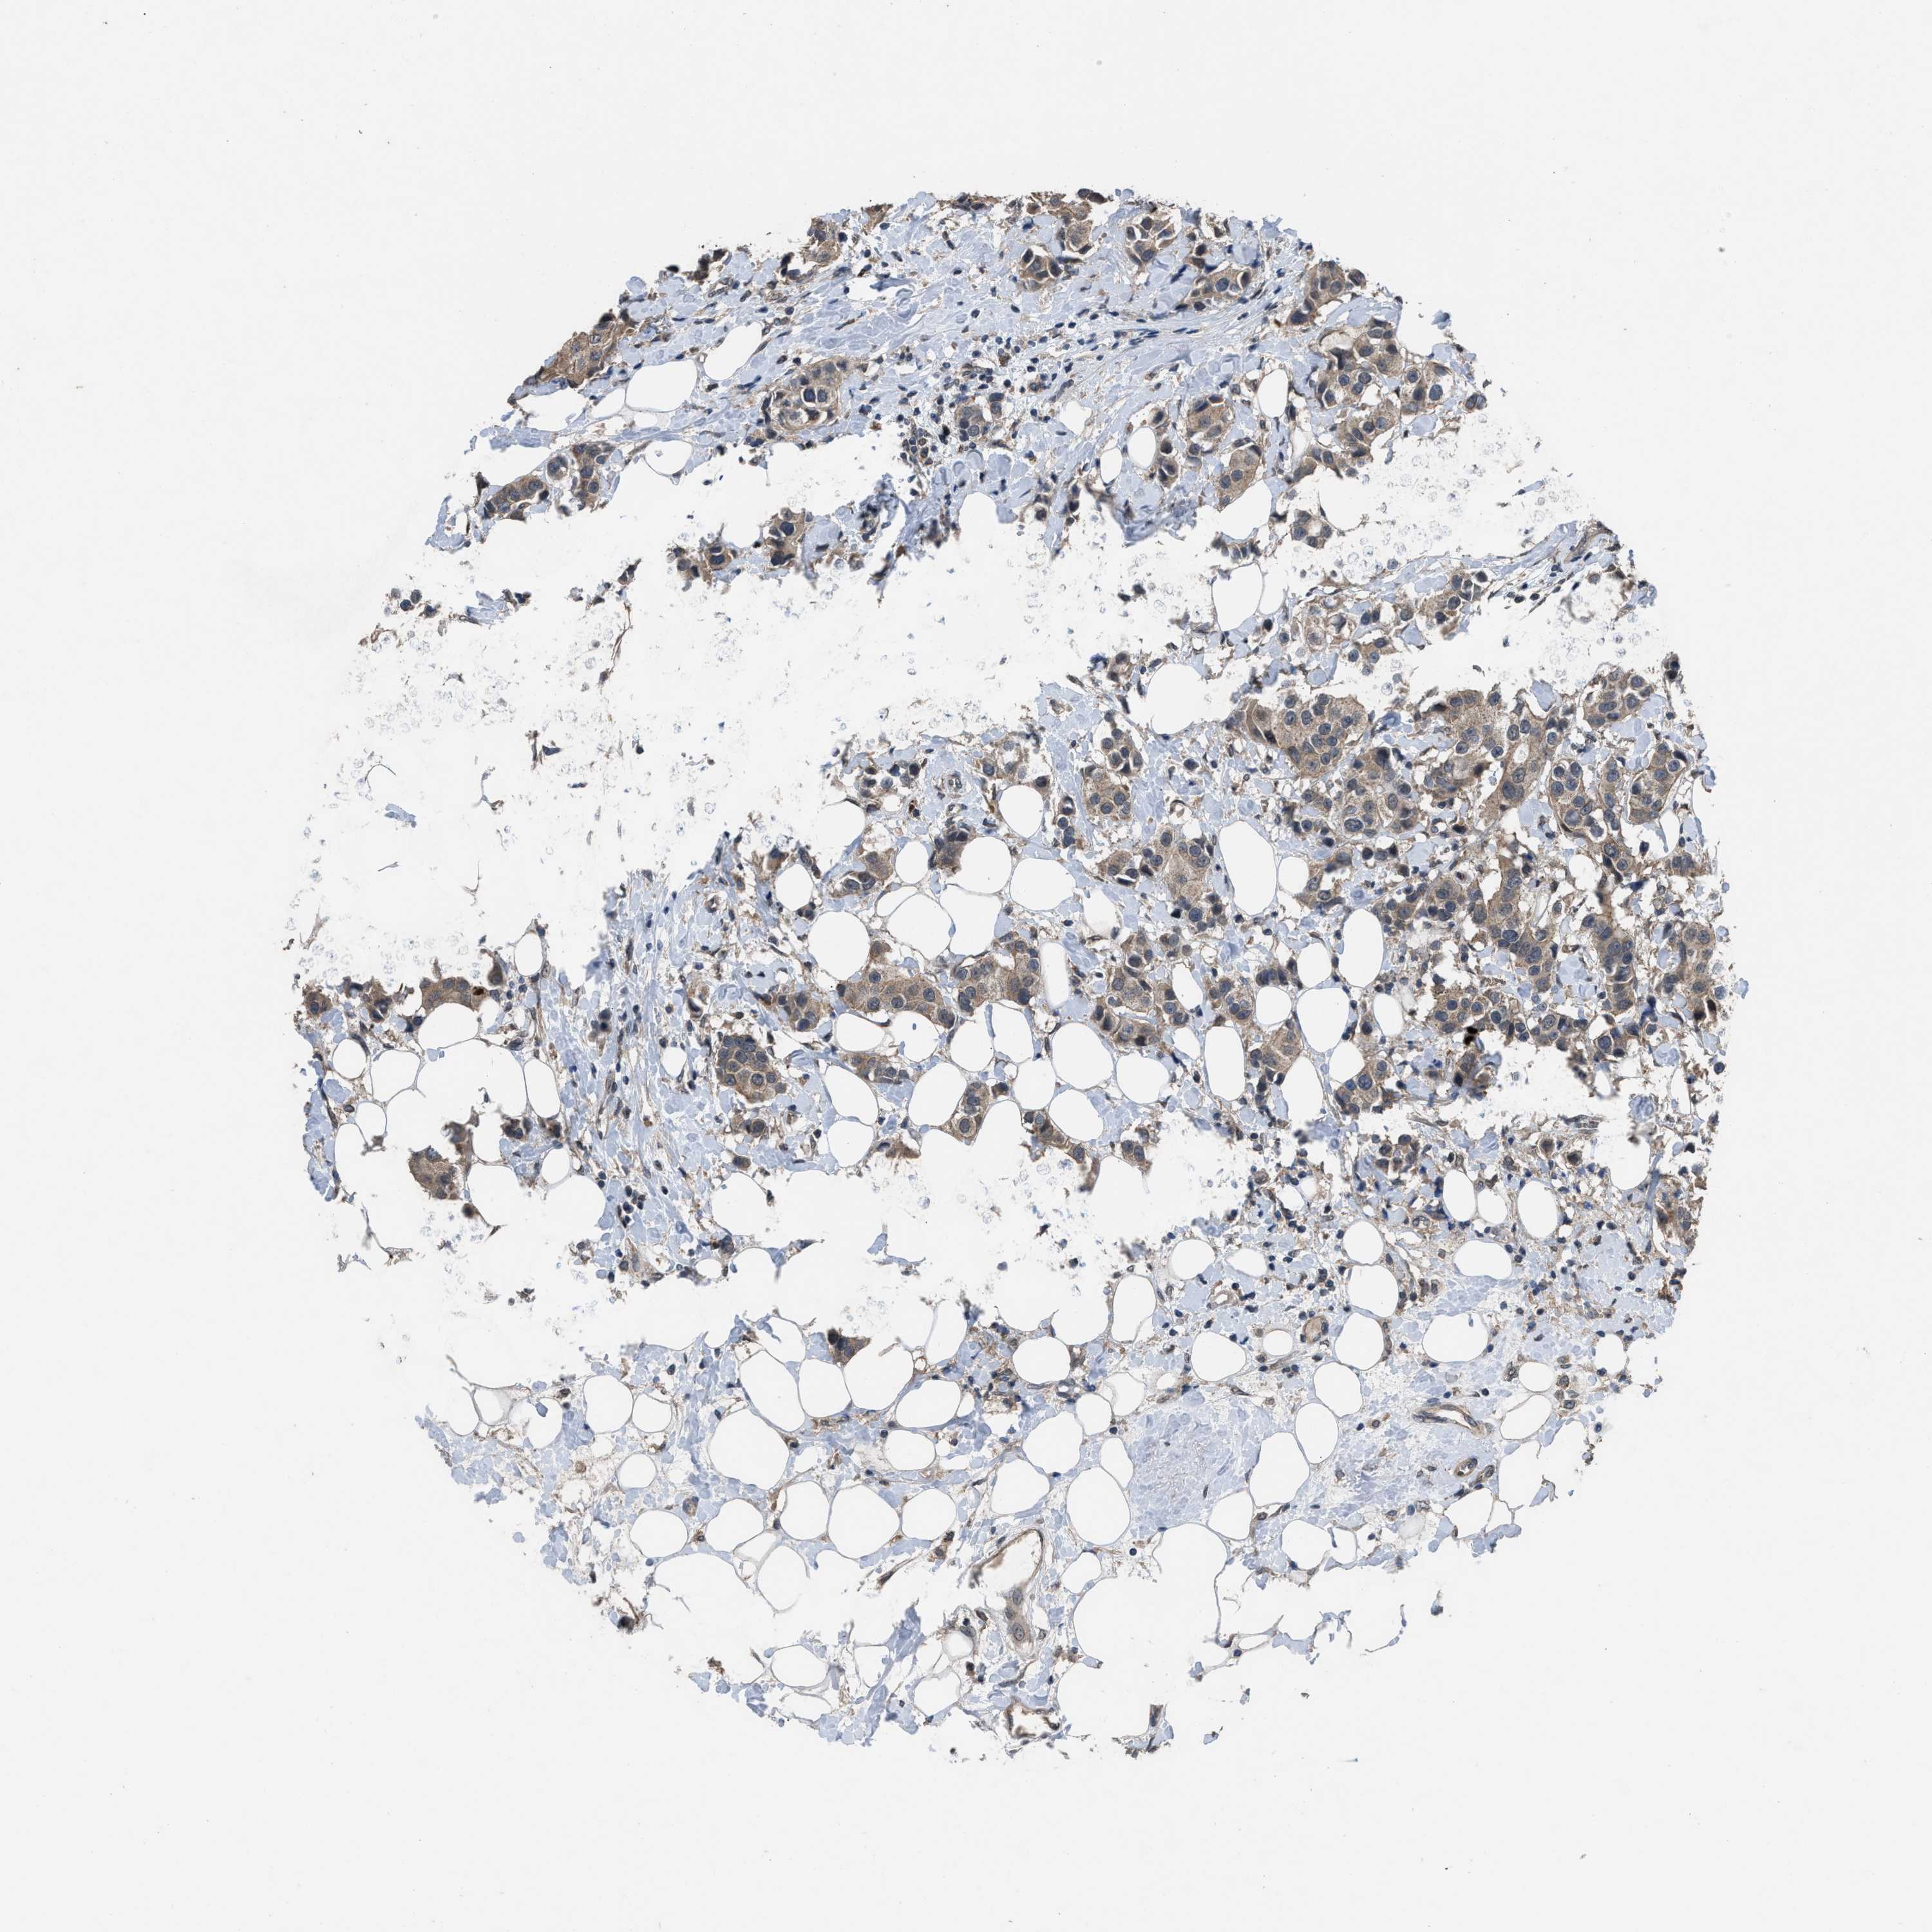

CANCER BREAST CANCER Show tissue menu

BRCA TCGA BRCA VALIDATION PROTEIN EXPRESSION